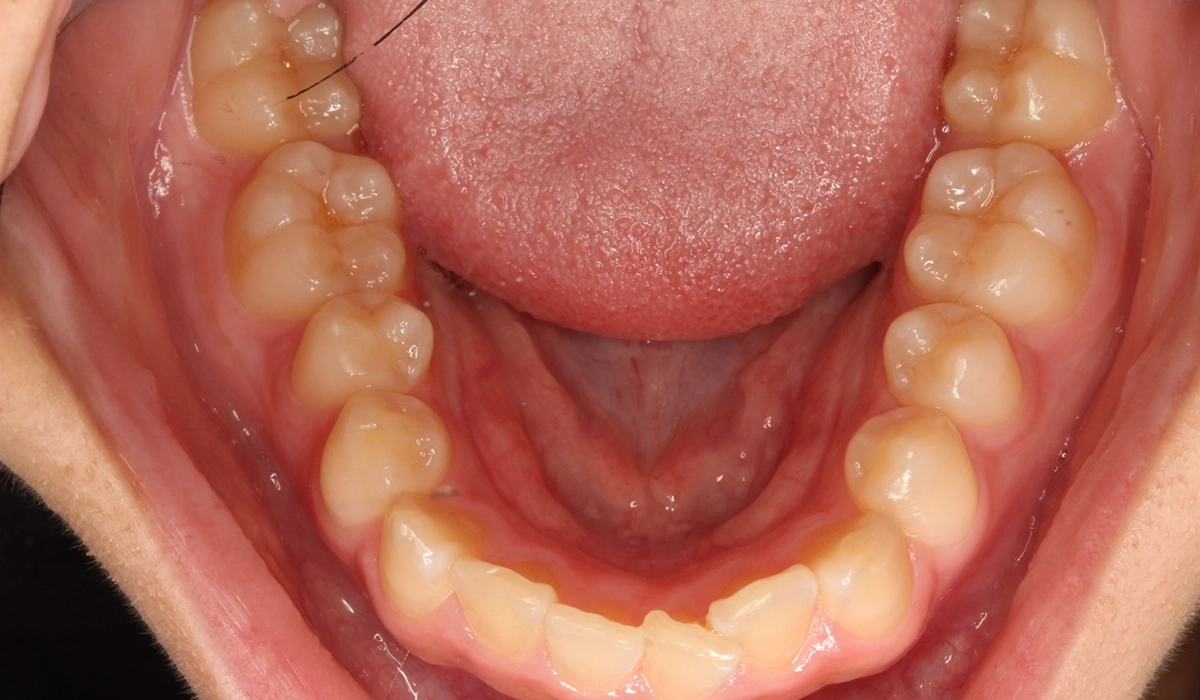

術前:下顎

術後:下顎